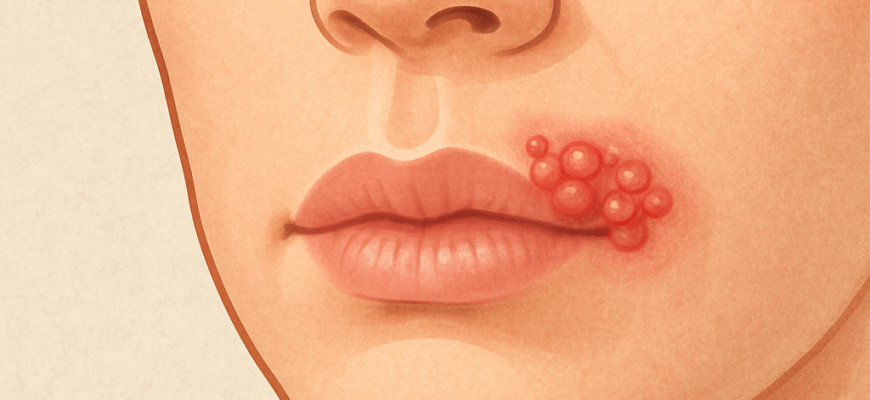

Рана на губі: чим лікувати і як боротися вдома Рана на губі—це одна з тих дрібниць, яка може добре зіпсувати настрій. Вона болить, заважає їсти, а іноді